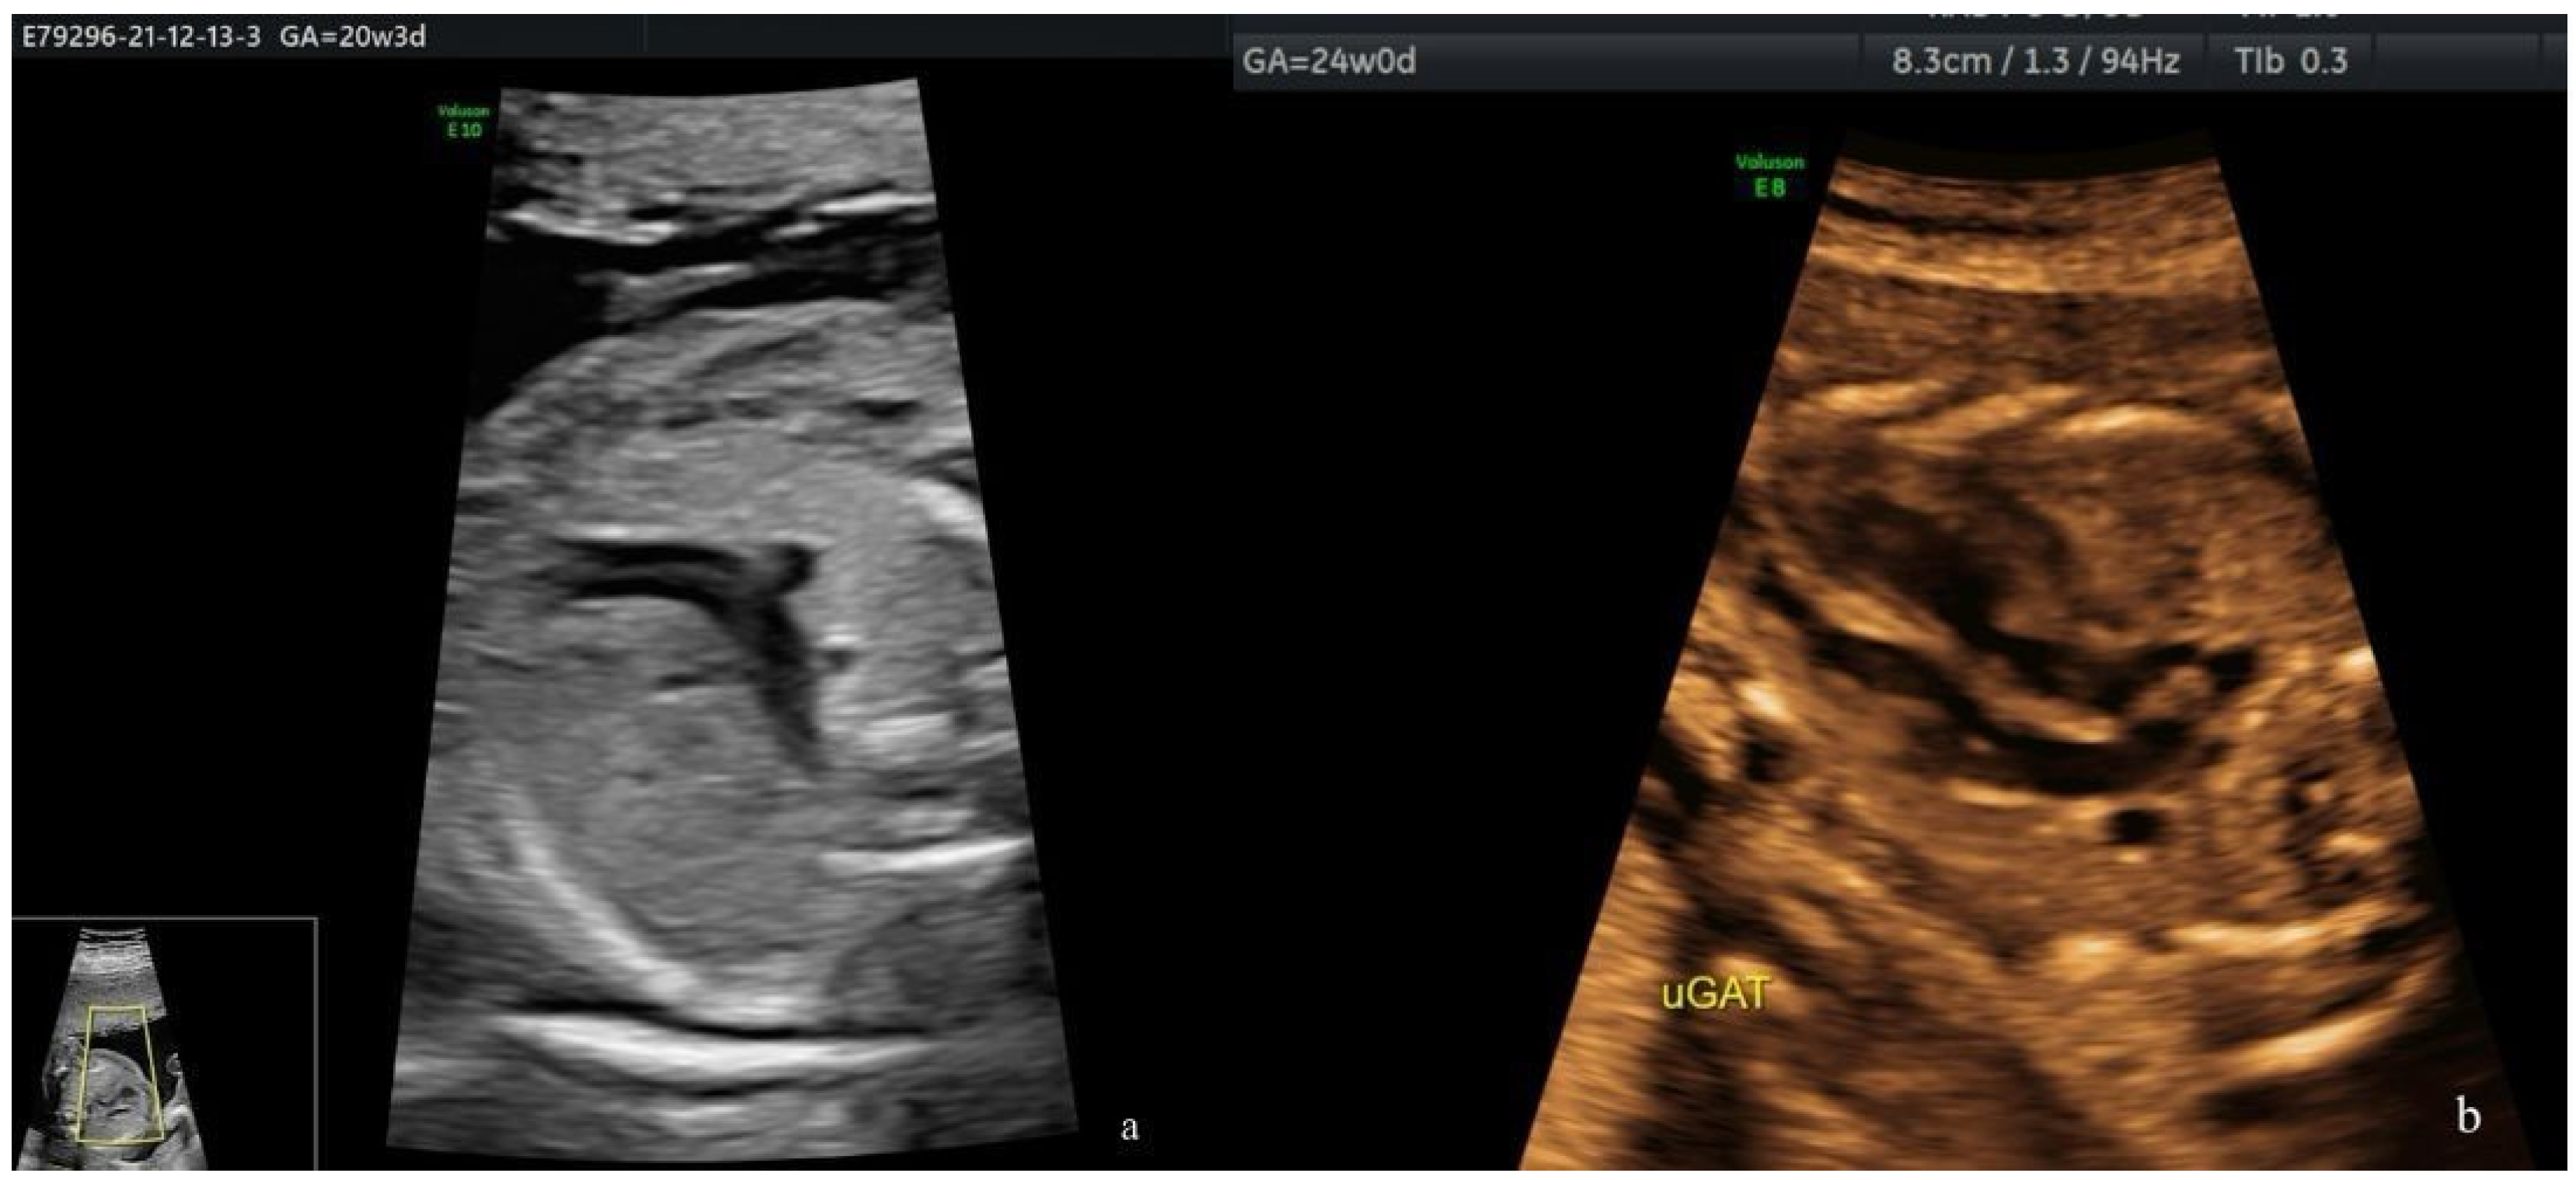

- The “reverse boomerang sign”—the reverse curvature of the right ventricle outflow tract (RVOT) at the level of the 3VT view in a TGA case.